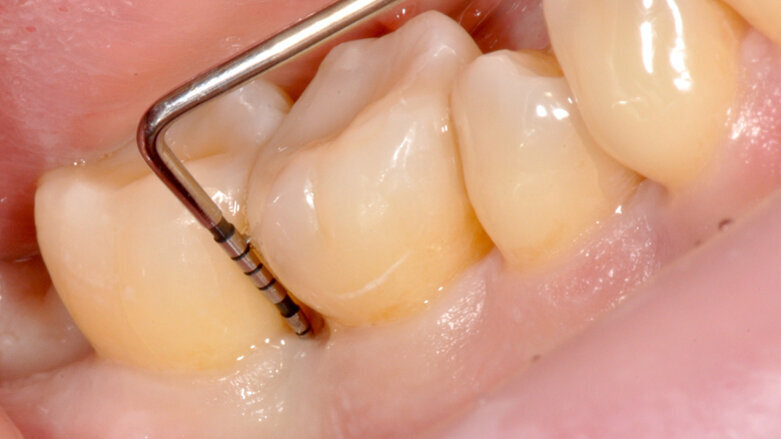

Fig. 4 - Sondaggio DV dell’elemento 4.6 di 9 mm.

Tuttavia, nei siti DV e MV degli elementi 4.6. e 4.7 si riscontra nuovamente BOP e SOP positivo. Si decide dunque di effettuare un intervento di chirurgia ricostruttiva, finalizzato alla chiusura del difetto intra-osseo e programmato ad una settimana dalla seduta di richiamo di igiene orale professionale (GBT®). Dopo uno sciacquo per 60 secondi con collutorio a base di Clorexidina 0.12% e Cloruro di Cetilpiridinio (Paroex® GUM®), si esegue anestesia locale plessica con Articaina 4% con adrenalina 1:100.000 e disegno di un lembo M-MIST (Modified-Micro Invasive Surgical Technique)5. La scelta di questo tipo di lembo è volta alla massima preservazione della vascolarizzazione del sito chirurgico e al mantenimento della papilla interdentale.